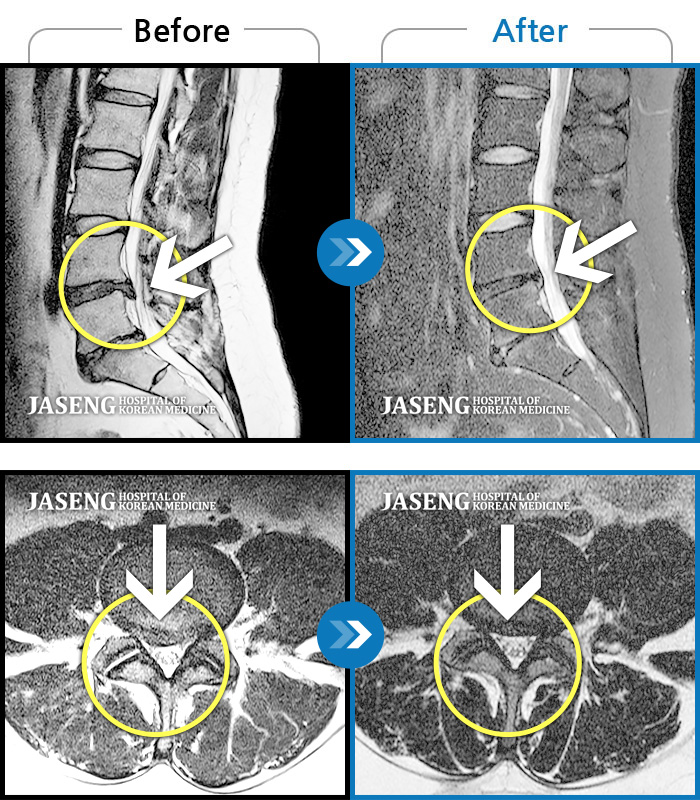

목디스크

도움받은 사례

인천 · 강아현 원장

처음 내원시 목에서 등으로 이어지는 통증 및 우측 팔 저림 증상이 심했고, 약간의 근력저하도 동반되어 일상생활이 어려운 상태였습니다.

촬영시기

2024.04.06 ~ 2024.11.16

2024.11.22

조회수 17,047